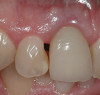

Figure 21   Gingival zenith planning: The location of the gingival zenith for this missing lateral incisor is not fully evident during initial clinical evaluation (Fig 21). Subsequent diagnostic waxing reveals the position of the planned gingival zenith (Fig 22). A thermoplastic template captures the position of the zenith and enables transferring this location to the clinical environment (Fig 23 and Fig 24). Final crown contours are defined by soft-tissue form (Fig 25).

Figure 21

Figure 22  Gingival zenith planning: The location of the gingival zenith for this missing lateral incisor is not fully evident during initial clinical evaluation (Fig 21). Subsequent diagnostic waxing reveals the position of the planned gingival zenith (Fig 22). A thermoplastic template captures the position of the zenith and enables transferring this location to the clinical environment (Fig 23 and Fig 24). Final crown contours are defined by soft-tissue form (Fig 25).

Figure 22

Figure 25  Gingival zenith planning: The location of the gingival zenith for this missing lateral incisor is not fully evident during initial clinical evaluation (Fig 21). Subsequent diagnostic waxing reveals the position of the planned gingival zenith (Fig 22). A thermoplastic template captures the position of the zenith and enables transferring this location to the clinical environment (Fig 23 and Fig 24). Final crown contours are defined by soft-tissue form (Fig 25).

Figure 25